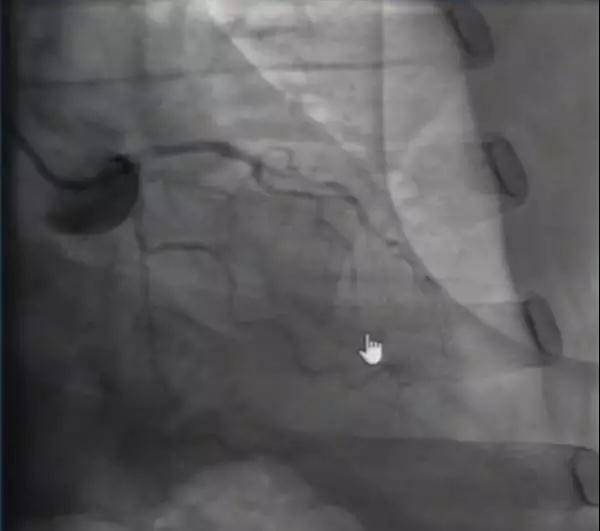

患者入CCU后,行冠脉造影检查结果如图5、图6,冠脉内注射硝酸甘油后,结果如图7、图8,考虑冠脉痉挛。术后给予地尔硫䓬持续泵点。当天17:15,患者再发胸闷、胸痛、大汗,心电图提示下壁导联ST段抬高,心率50次/分(图9),将泵点地尔硫䓬加量至症状缓解。17:48,患者再次诉胸闷、胸痛不缓解,心电图示三度房室传导阻滞,加速性异位心律(图10),予硝酸异山梨酯泵点,同时静脉补钾、强化他汀及尼可地尔稳定斑块及内皮功能,植入临时起搏器,2天后患者症状完全缓解,拔除临时起搏器。后患者未再发胸痛、胸闷,亦未有恶性心血管事件发生,将钙离子拮抗剂及硝酸酯类药物静脉给药逐渐向口服过渡。调整药物治疗方案:地尔硫䓬(早180 mg 晚90 mg)、硝酸异山梨酯60 mg Qd,阿托伐他汀40 mg Qd,阿司匹林100 mg Qd,尼可地尔5 mg Tid。考虑患者症状发作时存在恶性心律失常,建议置入起搏器,但患者明确拒绝。

图5

图6

图7

图8